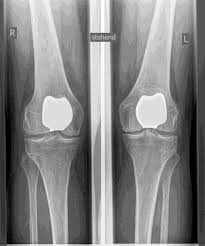

REEMPLAZO DE LA ARTICULACIÓN KNEAP (PFJ)

Las alteraciones de la movilidad o la inestabilidad, así como la forma de la rótula (displasia), pueden provocar daños en el cartílago y osteoartritis AISLADA EN LA articulación femororrotuliana. SI LOS OTROS COMPARTIMIENTOS ESTÁN LIBRES DE ARTROSIS, existe la posibilidad de realizar un reemplazo articular parcial aislado de la articulación rotuliana posterior.